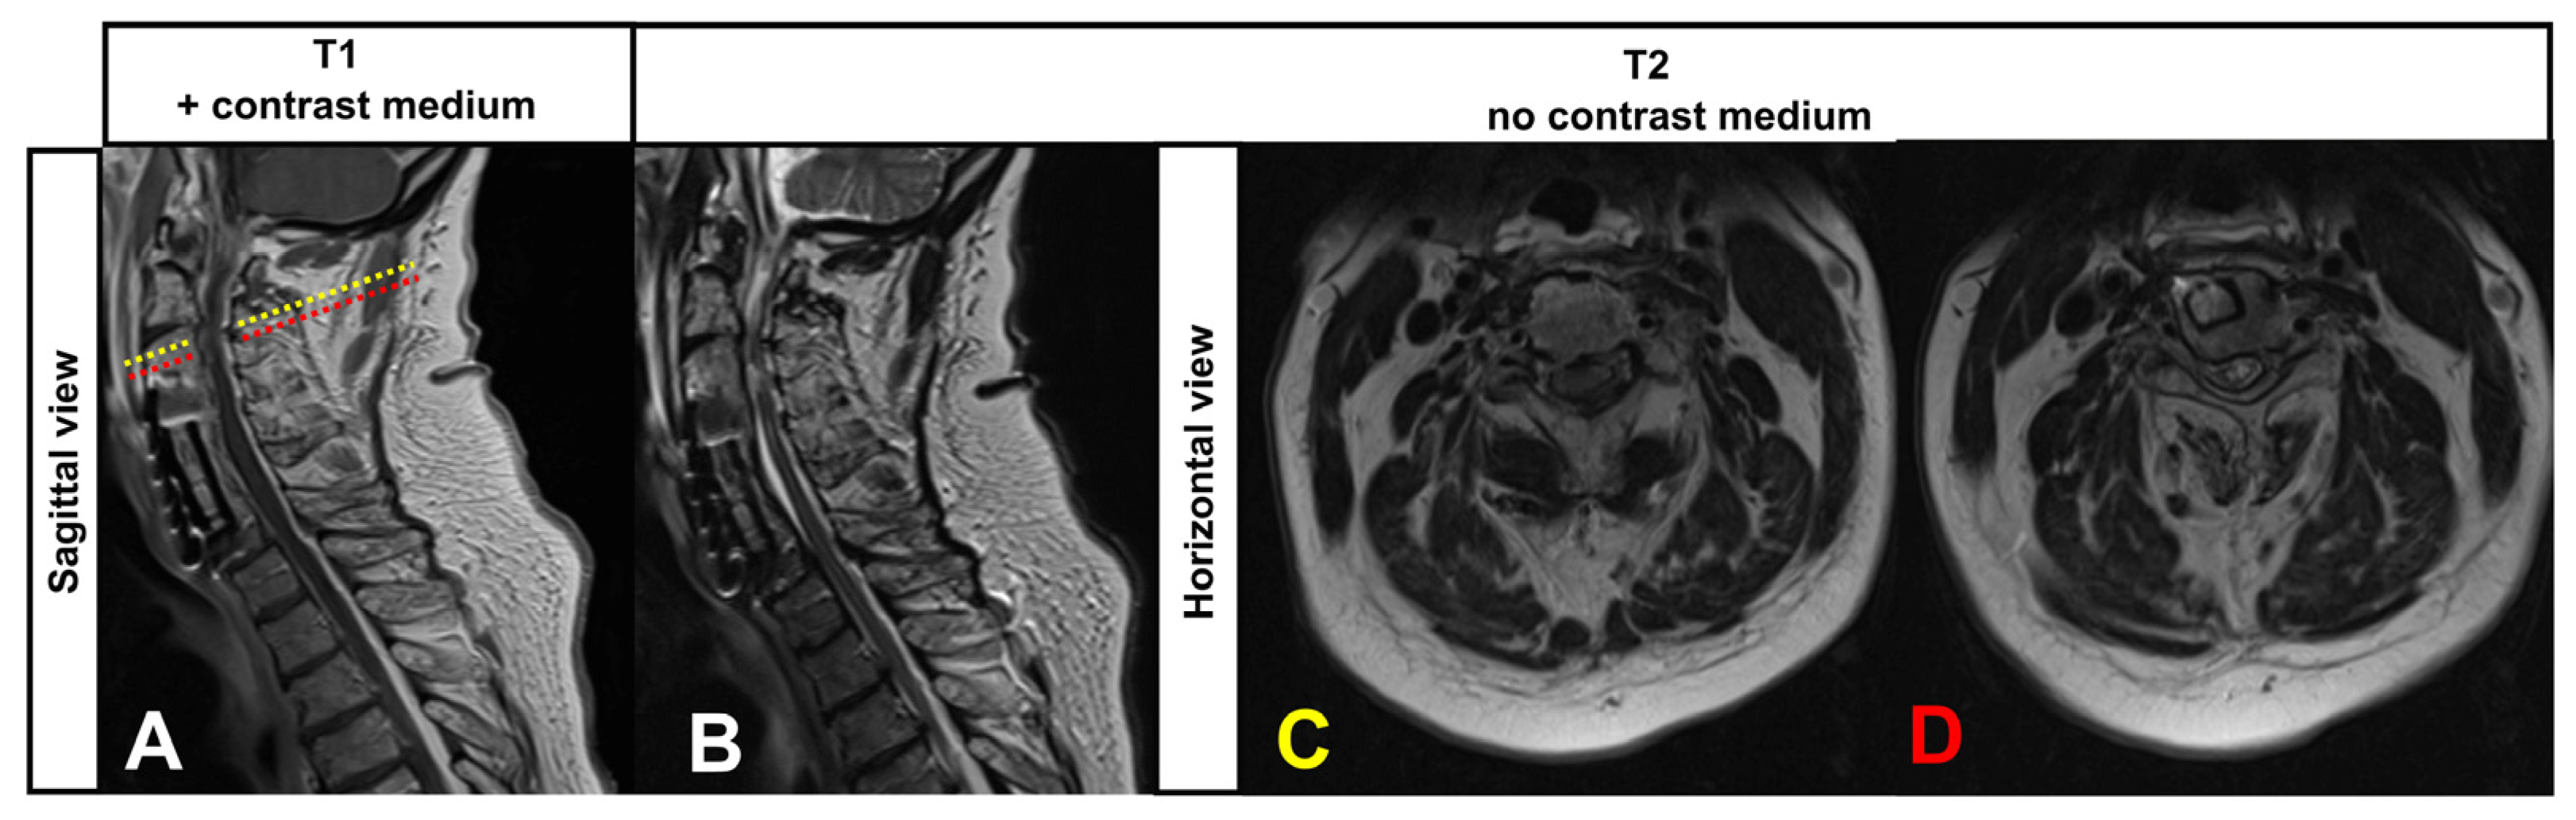

We here report on a 62-year-old male patient who presented with increasing subacute neurological deterioration of a known tetra-paresis and impoverishment of speech production within one week. A cervical spinal canal stenosis (multi-segmental with consecutive myelomalacia and attempt at surgical care, Figure 1A–D), as well as right frontobasal parenchymal defects following subarachnoid hemorrhage with consecutive ventricular congestion, ventriculoperitoneal shunt insertion in 2006 and pituitary insufficiency, were known from the previous medical history. Shortly before admission, the patient was wheelchair-mobile, could walk with support, and had speech production described as largely normal and adequate. There were no traumatic events that could explain an increase in tetraparesis.

Figure 1.

Cervical spinal stenosis and surgical treatment in the ventral area of cervical vertebrae 3/4. The cervical stenosis (Kang grade 3) and myelopathy were stable compared to previous MRIs. (A,B) Sagittal view. Levels of the horizontal slides (C,D) are indicated with dotted lines: in yellow is the level of the stenosis (C), and in red is the level of the myelomalacia directly caudal to the stenosis (D).

An additional MRI of the spinal cord showed myelopathy in the T2-weighted images at the level of cervical vertebra 3 and a narrowed spinal canal (Kang grade 3) constant to the previous findings 5 years ago (see Figure 1A–D) and showed no signs of recent alterations including trauma-related changes. Laboratory findings on admission showed an elevated CRP, pancytopenia, leukocytopenia, and thrombocytopenia due to sepsis. The hormone axes were largely normal on day 3 in the context of pituitary insufficiency. A lumbar puncture at the level of lumbar vertebrae 3 and 4 to exclude cerebral infection revealed a marked cytoalbumin dissociation (protein 938 mg/dL, albumin 7670 mg/L, 4 leucocytes/µL, lactate slightly increased with 2.5 mmol/L, glucose regular 50 mg/dL, xanthochrome color of the CSF, details see Table 1). IL6 in the CSF was slightly increased by 52 ng/L.